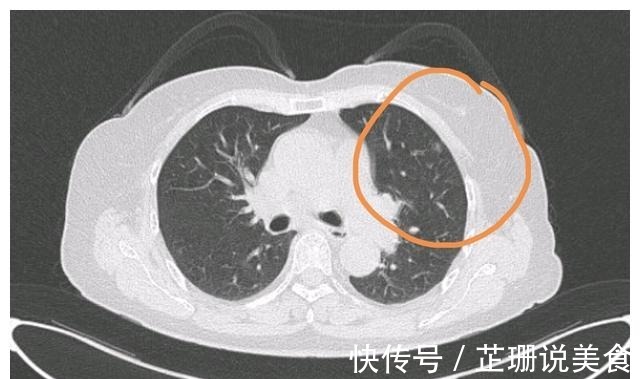

可是,当这一次体检的报告出来后,刘医生不淡定了,在父亲的肺部CT上,能明显看到有一个直径在1.5cm左右的边境不清晰的阴影,多年的临床经验让刘医生一下子就明白了,这是肺转移癌,不过好在属于早期,问题并不太大。看着父亲疲惫的双眼和满头白发,刘医生实在想不到为什么癌症病魔会接二连三地找上这个普通且勤劳的农民。沉默半晌,刘医生还是开口了:“爸,你这肺里有个结节,可能还要再做一次手术”。很明显,听到儿子说的话后,刘父本就不高大的身影又瞬间矮了下去,刘医生很心疼,正想安慰两句没事的时候,刘父开口了:“是转移了吧,别费劲了,反正年纪也大了”。